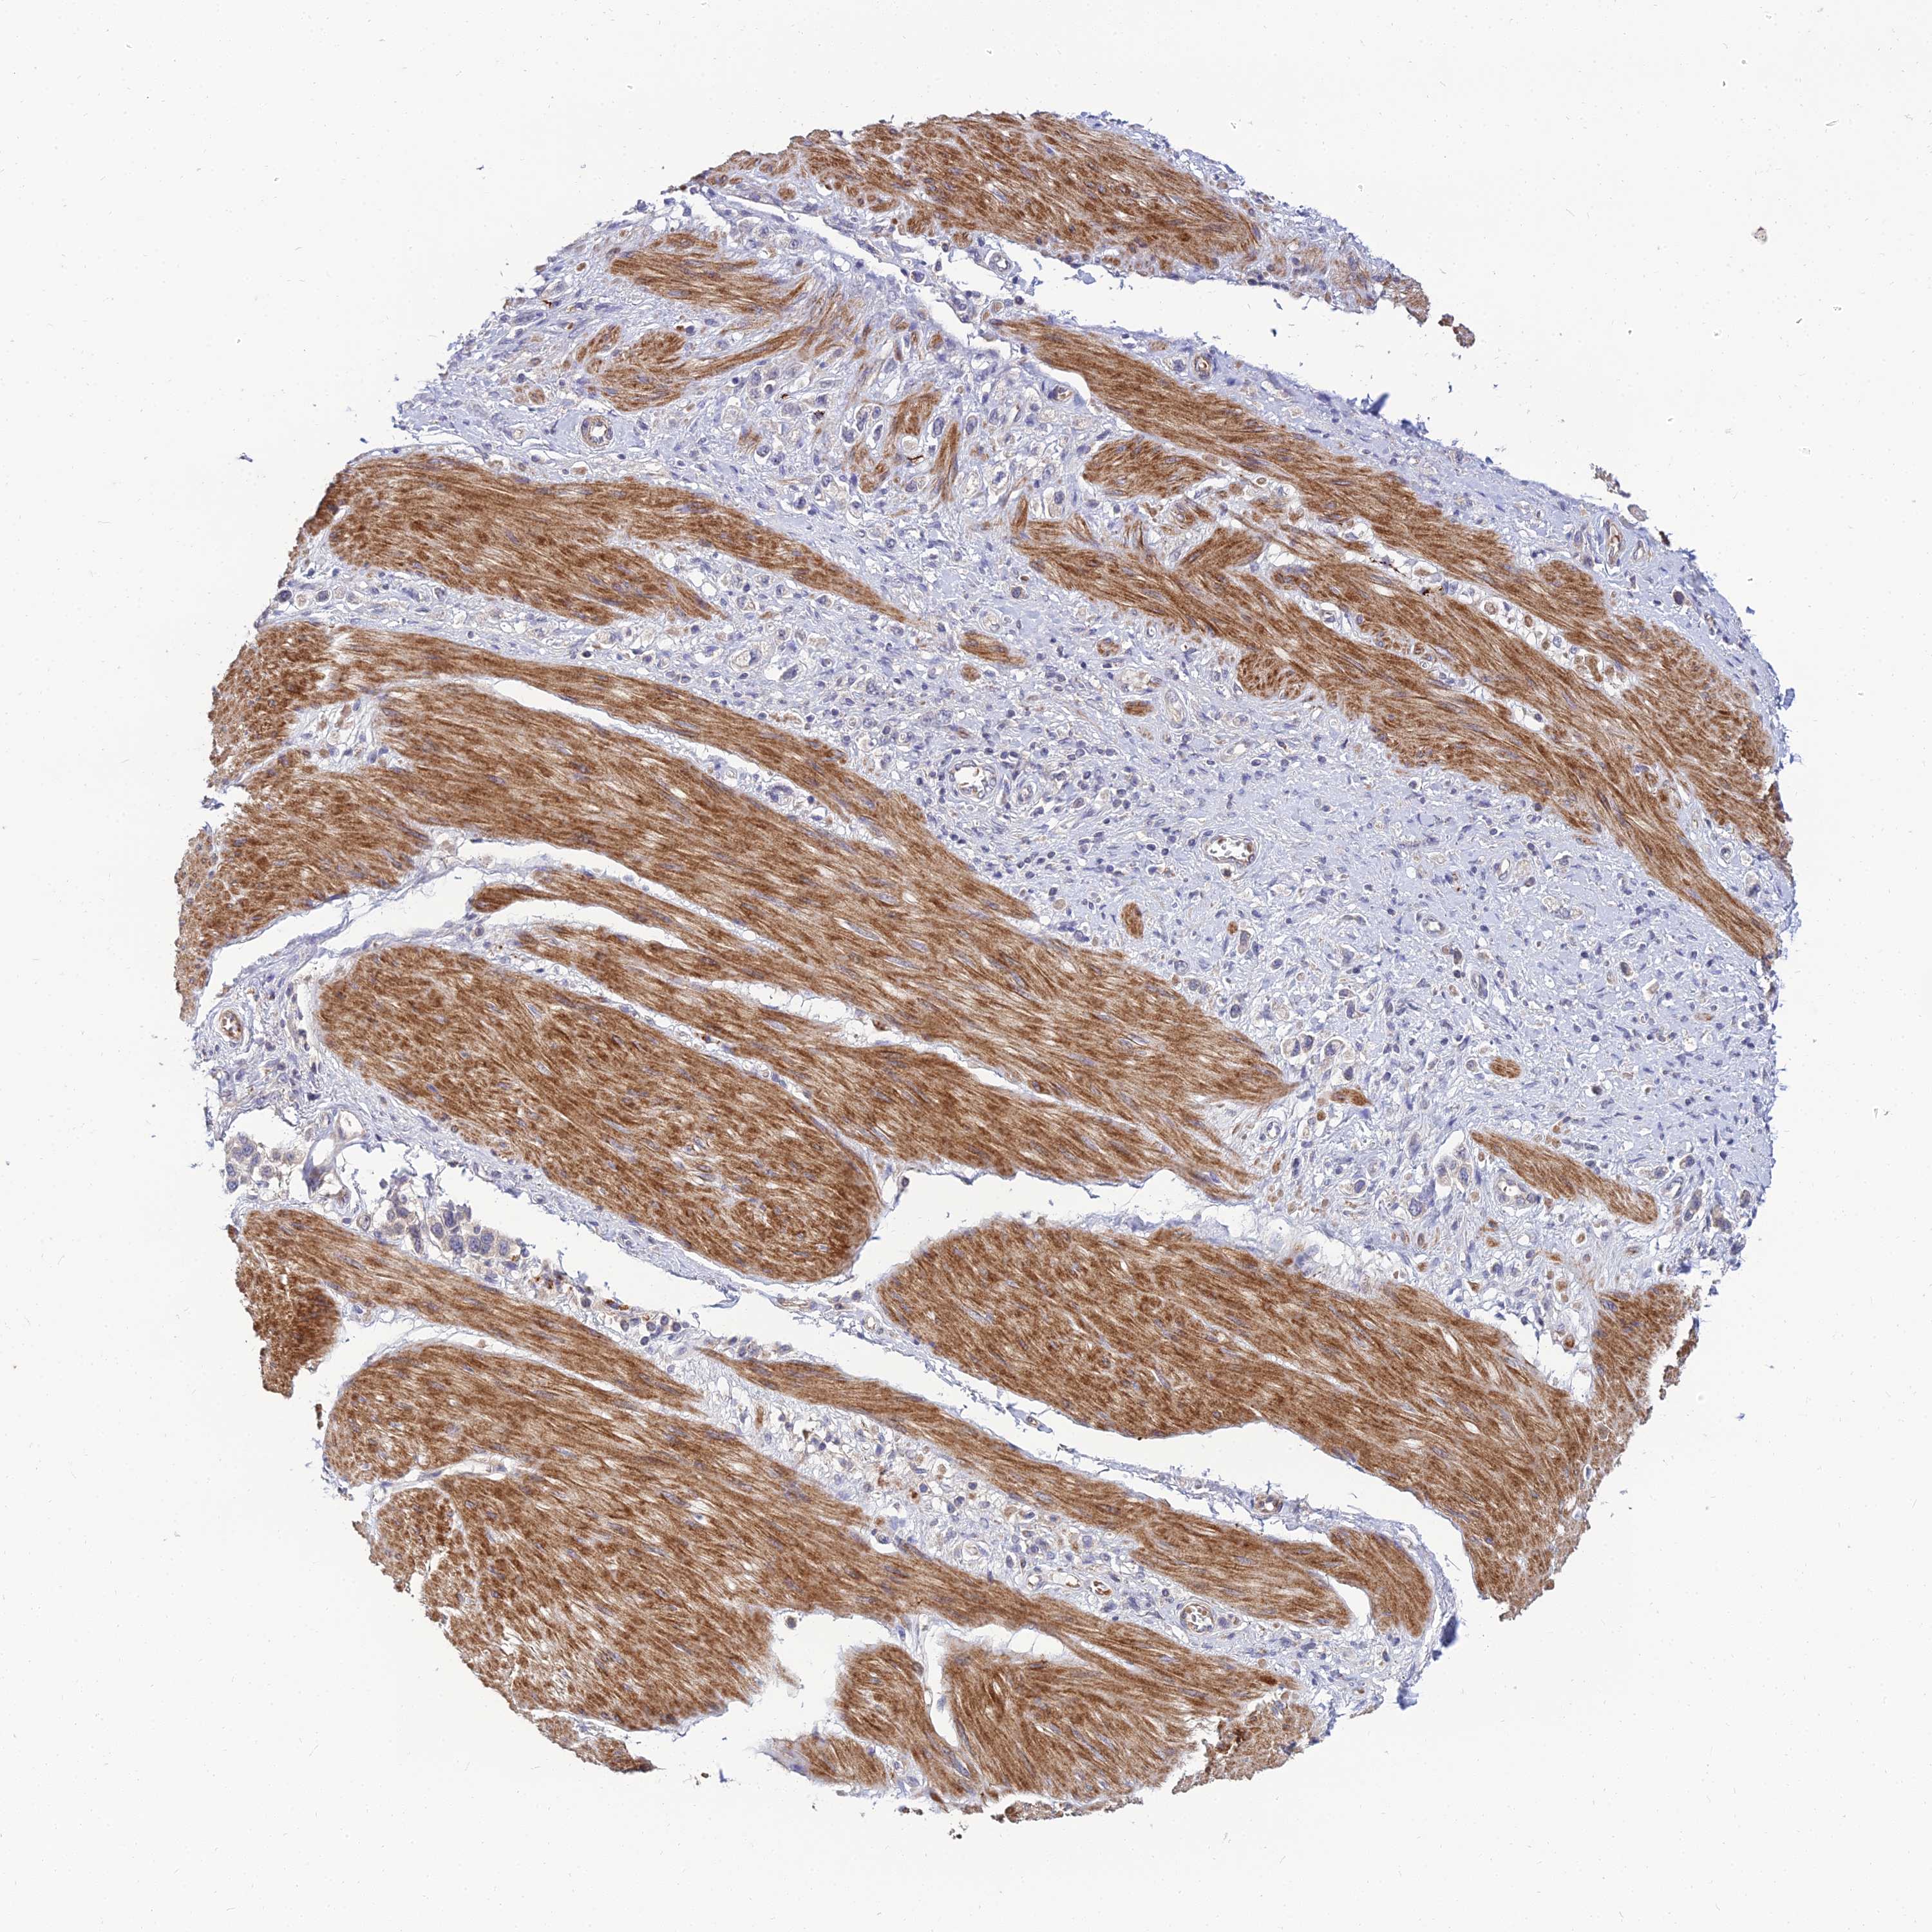

STOMACH CANCER - Protein expressioni

A mouse-over function shows sample information and annotation data. Click on an image to view it in a full screen mode. Samples can be filtered based on level of antibody staining by selecting one or several of the following categories: high, medium, low and not detected. The assay and annotation is described here.

Note that samples used for immunohistochemistry by the Human Protein Atlas do not correspond to samples in the TCGA dataset.

Antibody stainingi

Antibody staining in the annotated cell types in the current human tissue is reported as not detected, low, medium, or high, based on conventional immunohistochemistry profiling in selected tissues. This score is based on the combination of the staining intensity and fraction of stained cells.

Each image is clickable and will lead to virtual microscopy that enables deeper exploration of all samples and also displays staining intensity scores, fraction scores and subcellular localization as well as patient and tissue information for each sample.

Antibody HPA044572

Antibody HPA056798

Antibody CAB016733

Antibody CAB034368

Staining

High

Medium

Low

Not detected

Intensity

Strong

Moderate

Weak

Negative

Quantity

>75%

75%-25%

<25%

None

Location

Nuclear

Cytoplasmic/membranous

Cytoplasmic/membranous,nuclear

Adenocarcinoma, NOS